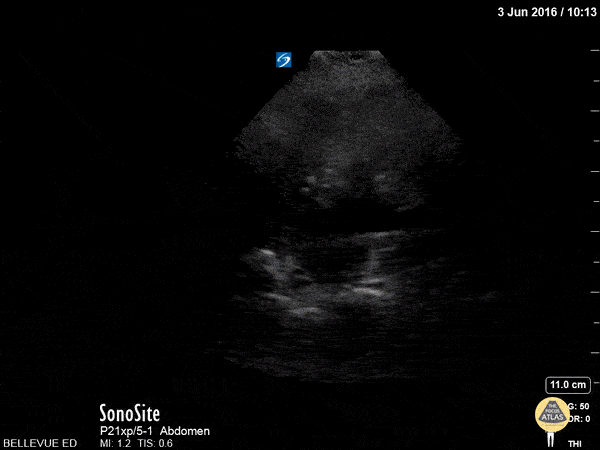

Renal/GU - LUQ Kidney Long Axis

This clip fans through the left kidney in long axis. The hyperechoic central area is the renal pelvis and calyces, the darker hypoechoic area surrounding it is the renal cortex. The renal pyramids are visible as anechoic triangles within the medulla. Deep to the kidney we see the hyperechoic spine;on the left of the screen the spleen comes in and out of view. Hannah Kopinksi and Dr. Lindsay Davis - NYU Emergency Medicine